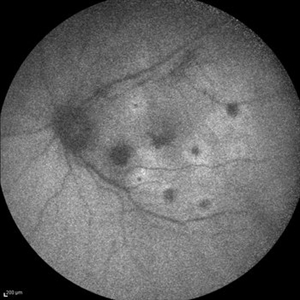

Best Disease Best DiseaseMar 9 2013 by Hamid Ahmadieh, MD Autofluorescence Imaging of the left eye of a 49-year-old man with decreased VA due to advanced Best disease. Photographer: Soodabeh Fooladin, Negah Eye Center, Tehran Imaging device: Heidelberg Spectralis Condition/keywords: autofluorescence imaging, Best disease